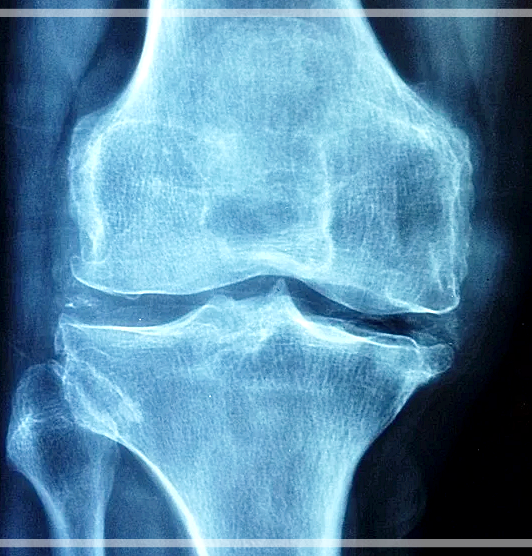

요즘 젊은 사람들도 허리디스크나 무릎, 목 등의 관절 통증을 호소하시는 분들이 많은 것 같습니다. 관절은 우리가 살면서 몸을 움직이는 거의 모든 동작에 사용이 되기 때문에 점점 닳기 마련입니다. 때문에 미리미리 관절 관리를 해놓아야 노년도 건강하게 보낼 수 있습니다.

관절염이 있는 연골을 정상 연골과 비교해보았더니 황 농도가 1/3 정도가 낮은 것이 확인이 되었다고 합니다. 그래서 msm을 섭취해주면 관절 건강에 도움이 될 수 있는 것인데요, 실제로 45~90세의 관절염 환자들을 대상으로 MSM을 섭취하게 하였더니 관절 통증과 뻣뻣함 등의 관절 기능의 불편함이 감소되었다는 실험 결과가 나타났어요.